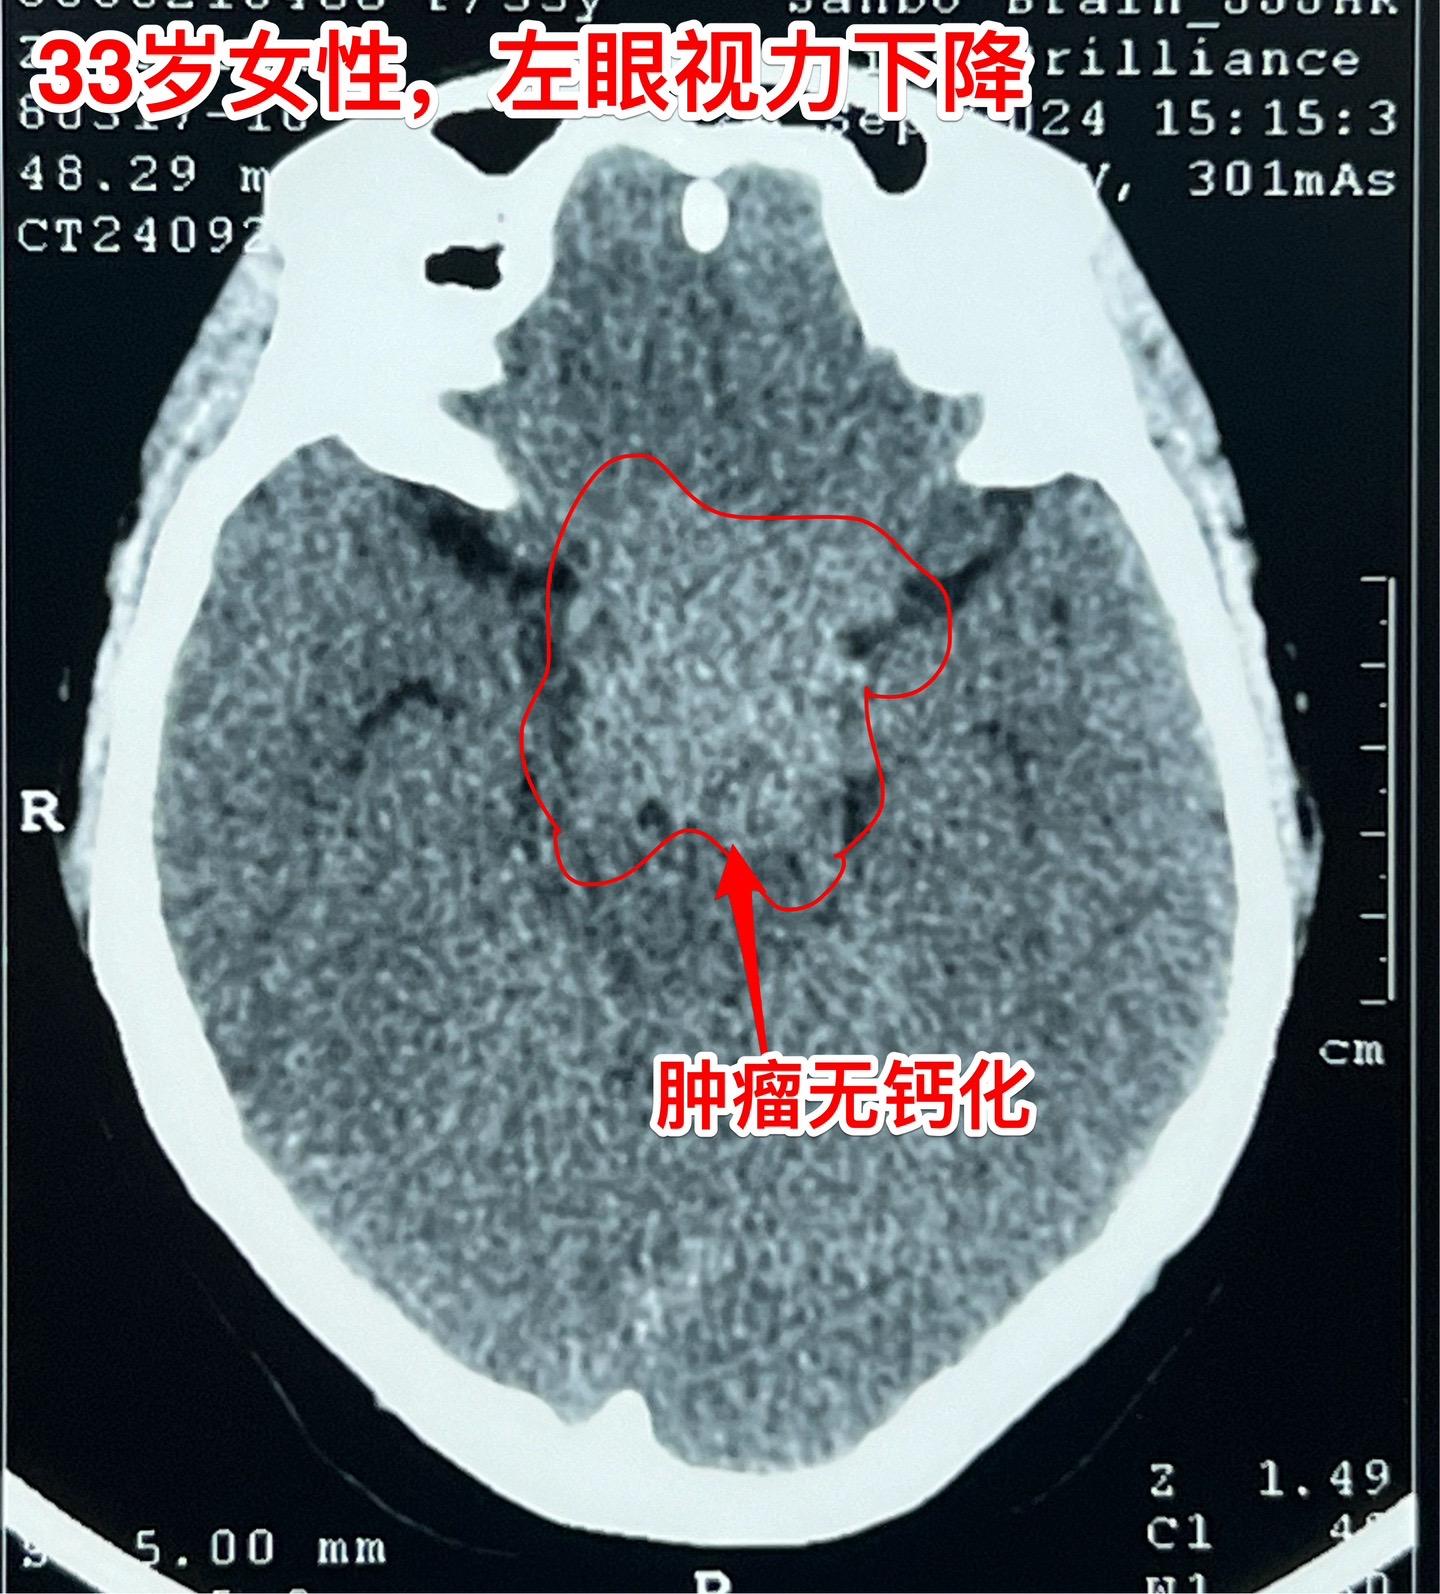

国庆节长假后第一天完成两个手术。一个手是33岁女性,来自云南省香格里拉。因左眼视力下降,到医院检查发现鞍区肿瘤,怀疑是颅咽管瘤。病人没有内分泌功能障碍。影像学上肿瘤是实性的,没有钙化,而且可以看见垂体信号。到底是什么肿瘤呢?今天手术中取肿瘤标本作快速冰冻病理检查,报告是垂体瘤。肿瘤得到完全切除,手术后病人视力好转了。 另一个手术是11岁男孩子,颅咽管瘤复发。经原切口翼点入路将肿瘤完全切除。术前磁共振只看见一个圆形肿瘤,术中发现除了这个肿瘤外还有5个散在的钙化斑,均得到完全切除。这样的散在钙化斑是潜在的危险因